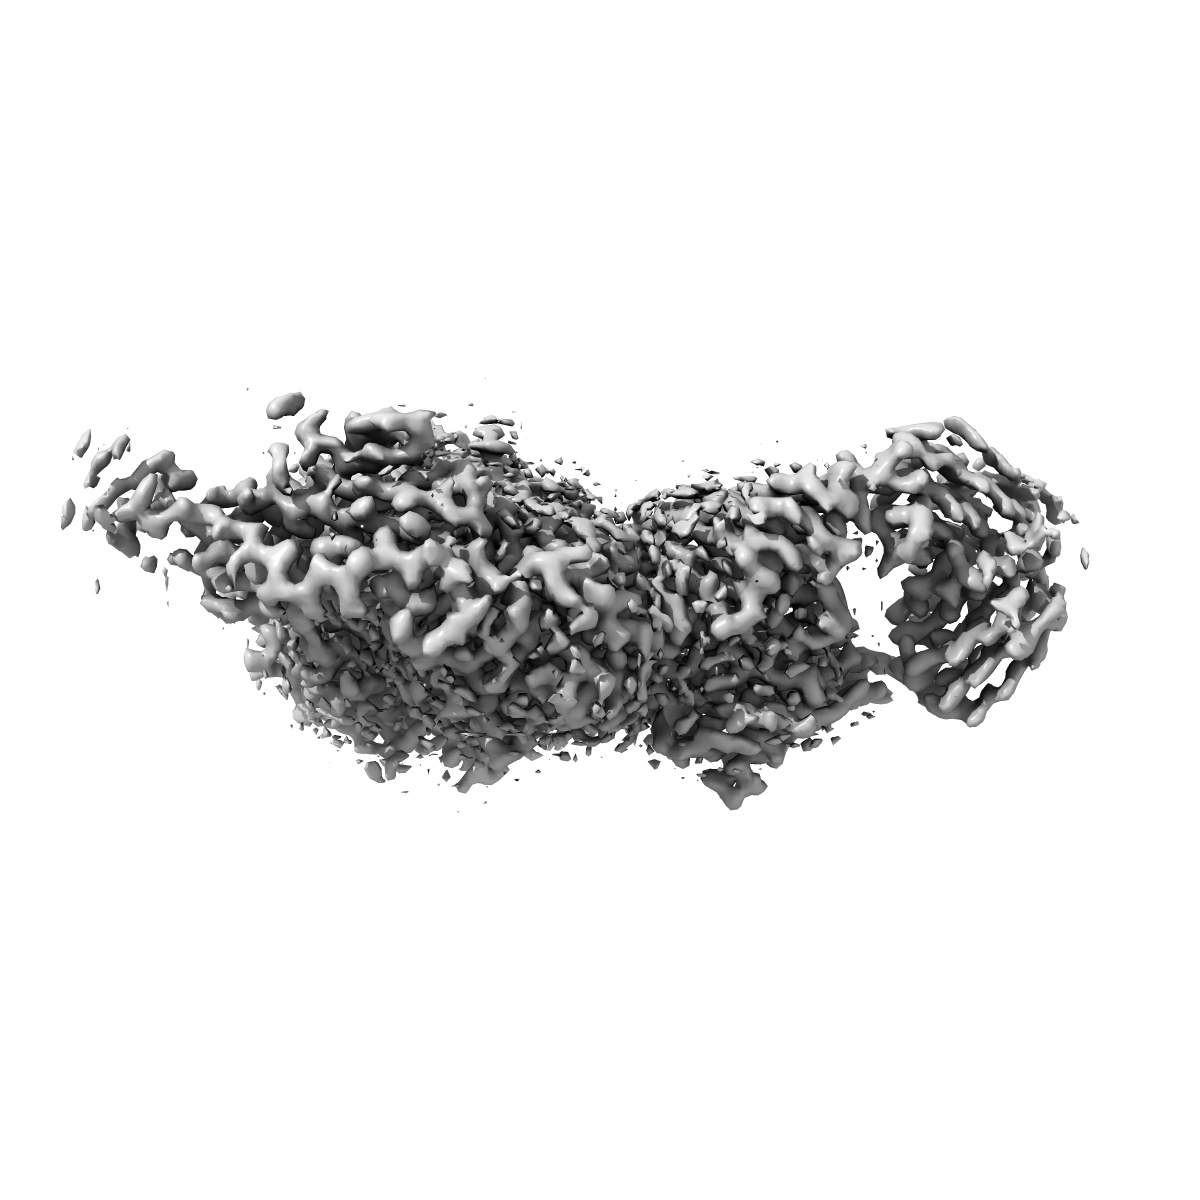

Cryo-EM structure of the integrin AlphaIIbBeta3-Abciximab complex

Cryo-Electron Microscopy Structure of the alpha IIb beta 3-Abciximab Complex.

Nesic D, Zhang Y, Spasic A, Li J, Provasi D, Filizola M, Walz T , Coller BS

(2020) Arterioscler Thromb Vasc Biol , 40 , 624 - 637